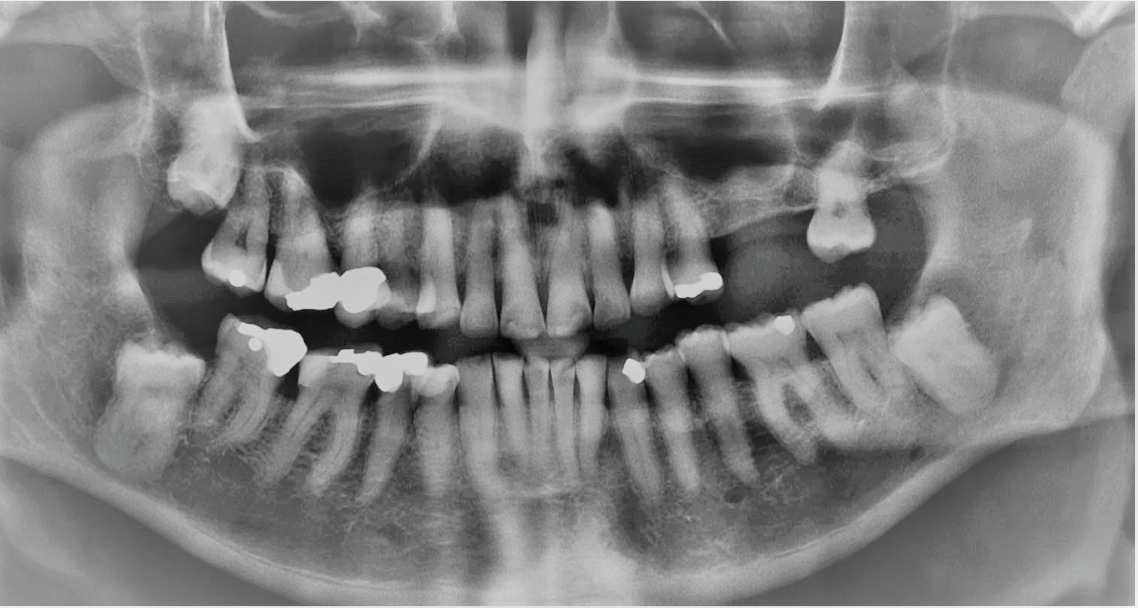

This healthy 64 year old male patient presented with missing teeth 25 and 26, which had been removed some years ago due to periodontal disease. Despite excellent oral health in general and thick biotype at the local sites of interest, there had been expansion of the maxillary sinus leading to only 4 mm of bone height at site 26. See diagnostic CBCT radiograph below.